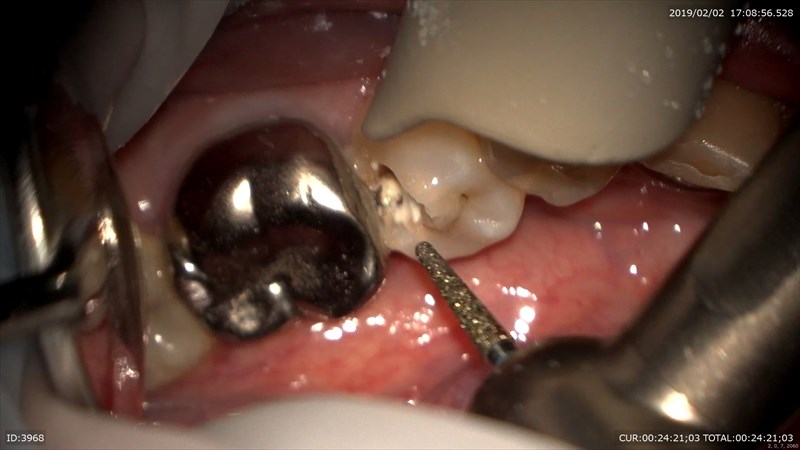

この症例は今年の初めにいらした方。

痛み(自発痛がででいました)がありみてもらいたいと。

あらま大きな虫歯。歯科ドックで神経まで達していると確認。

そこで私はMTAを使い